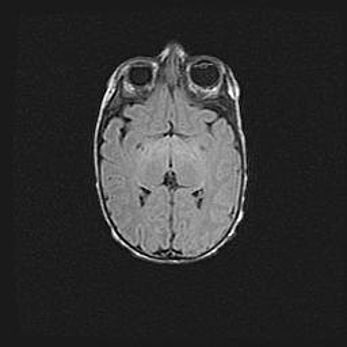

Церебральная ишемия II.

Возраст: 5 дней

Вес: 3400 г

Пол: женский

Окружность головы: 35 см

Срок гестации: 39 недель

Церебральная ишемия – это заболевание, характеризующееся недостаточностью (гипоксией) либо полным прекращением (аноксией) снабжения мозга кислородом по причине закупорки одного или нескольких сосудов. Это приводит к  что метаболическим расстройствам различной степени тяжести в тканях головного мозга, развитию коагуляционных некрозов и гибели нейронов.